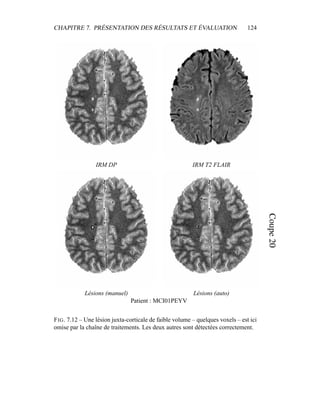

tion of white matter lesions in T2 FLAIR MRI of relapsing-remitting mul-

tiple sclerosis patients. In 20th Congress of the European Committee for

Treatment and Research in Multiple Sclerosis (ECTRIMS), Vienna, Austria,

October 2004.